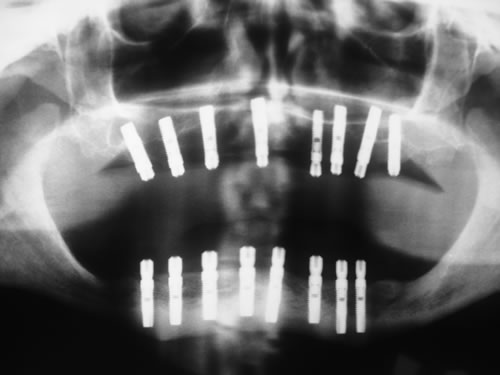

Bei der ersten Untersuchung in der Praxis hat Frau W. zunächst den Anamnesebogen ausgefüllt. Sie ist nie ernstlich krank gewesen und nimmt nur gelegentlich eine Kopfschmerztablette. In einem ausführlichen Gespräch berichtet sie ihrem Zahnarzt über die Schwierigkeiten mit den Prothesen. Nach einer ersten Untersuchung kann ihr der Zahnarzt Mut machen. Die Kieferverhältnisse sind zwar sehr ungünstig, doch so, dass eine Einpflanzung noch möglich ist. Die vorhandenen Prothesen weisen keine Mängel auf, finden aber keinen Halt. Beide Prothesen sollen nach der Einpflanzung weiter getragen werden. Nach einem Kieferabdruck wird eine Platte für den Unterkiefer angefertigt, auf der Metallkugeln befestigt sind. Sie wird wie eine Prothese eingesetzt, und es wird eine Röntgenaufnahme gemacht, die anschließend vom Zahnarzt genau vermessen wird. Es ergibt sich, dass noch eine Resthöhe von 15 mm vorhanden ist. Da auch die Breite des Kiefers ausreicht, wird ihr die Einpflanzung von vier künstlichen Zahnwurzeln empfohlen. Für ihre spezielle Kieferform ist dies die beste Lösung.

Für den Oberkiefer ist eine CT-Untersuchung notwendig, die ebenfalls mit einer Schablone durchgeführt wird. Auswertung, Planung und Implantations-Simulationen ergeben, dass sechs Implantate im vorderen Kieferabschnitt verankert werden können. Auch die Qualität des Knochens lässt eine Einpflanzung ohne weitere Maßnahmen zu. Diese Behandlung soll nach der Versorgung des Unterkiefers erfolgen.

Die zahnärztliche Untersuchung umfasst die Beurteilung der gesamten Mundhöhle, der Schleimhaut, der Zähne und der Kieferknochen. Wenn eine Einpflanzung in Erwägung gezogen wird, muss eine Röntgenmessaufnahme angefertigt werden. Dazu wird nach einem Kieferabdruck eine Planungsschablone hergestellt, in die Metallkörper (Kugeln oder Stifte) an den Stellen eingearbeitet sind, an denen eine Implantation geplant ist (Abb. 5.1, 5.2). Diese Platte wird in den Mund des Patienten eingesetzt und die Röntgenaufnahme angefertigt (Abb. 5.3, 5.4).

Da die Größe der Metallkörper, die auf der Aufnahme gut sichtbar sind, bekannt ist, kann aus dem Röntgenbild die zur Verfügung stehende Knochenhöhe sehr genau errechnet werden.

Mit der Entwicklung der Computertomographie (CT) und in jüngerer Vergangenheit der digitalen Volumentomographie (DVT) stehen Untersuchungsverfahren zur Verfügung, mit denen sehr viel einfacher und genauer das Knochenangebot vermessen werden kann. Von dem Patienten wird in einer Klinik oder Praxis, die über die entsprechenden Möglichkeiten verfügt, ein Spezialröntgenbild (DVT/CT) des Ober-, seltener des Unterkiefers, angefertigt. Dieses spezielle Röntgenbild dauert für einen Kiefer 20 Sekunden. Der große Vorteil liegt darin, dass der gesamte Kiefer durch den Computer in über 100 Schnitten abgebildet werden kann. Auf diesen Schnittbildern können Höhe und Breite des Knochens direkt abgemessen werden (Abb. 5.5).